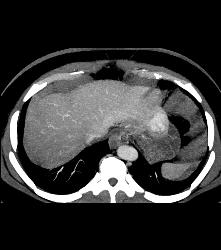

Glomus Tumor